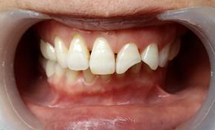

深圳博愛曙光口腔專家表示:採取補牙術是為了阻止齲齒繼續惡化。所謂補牙就是採用用人造物質修補牙體缺損的方法,用於修補的物質叫充填材料。凡因齲齒、楔狀缺損、外傷等造成牙體組織缺損者都需要修補,以恢復其外形和功能。

全面口腔检查,并根据龋齿的数量、疗位、龋病的病变程度制定最佳的补牙修复方案。